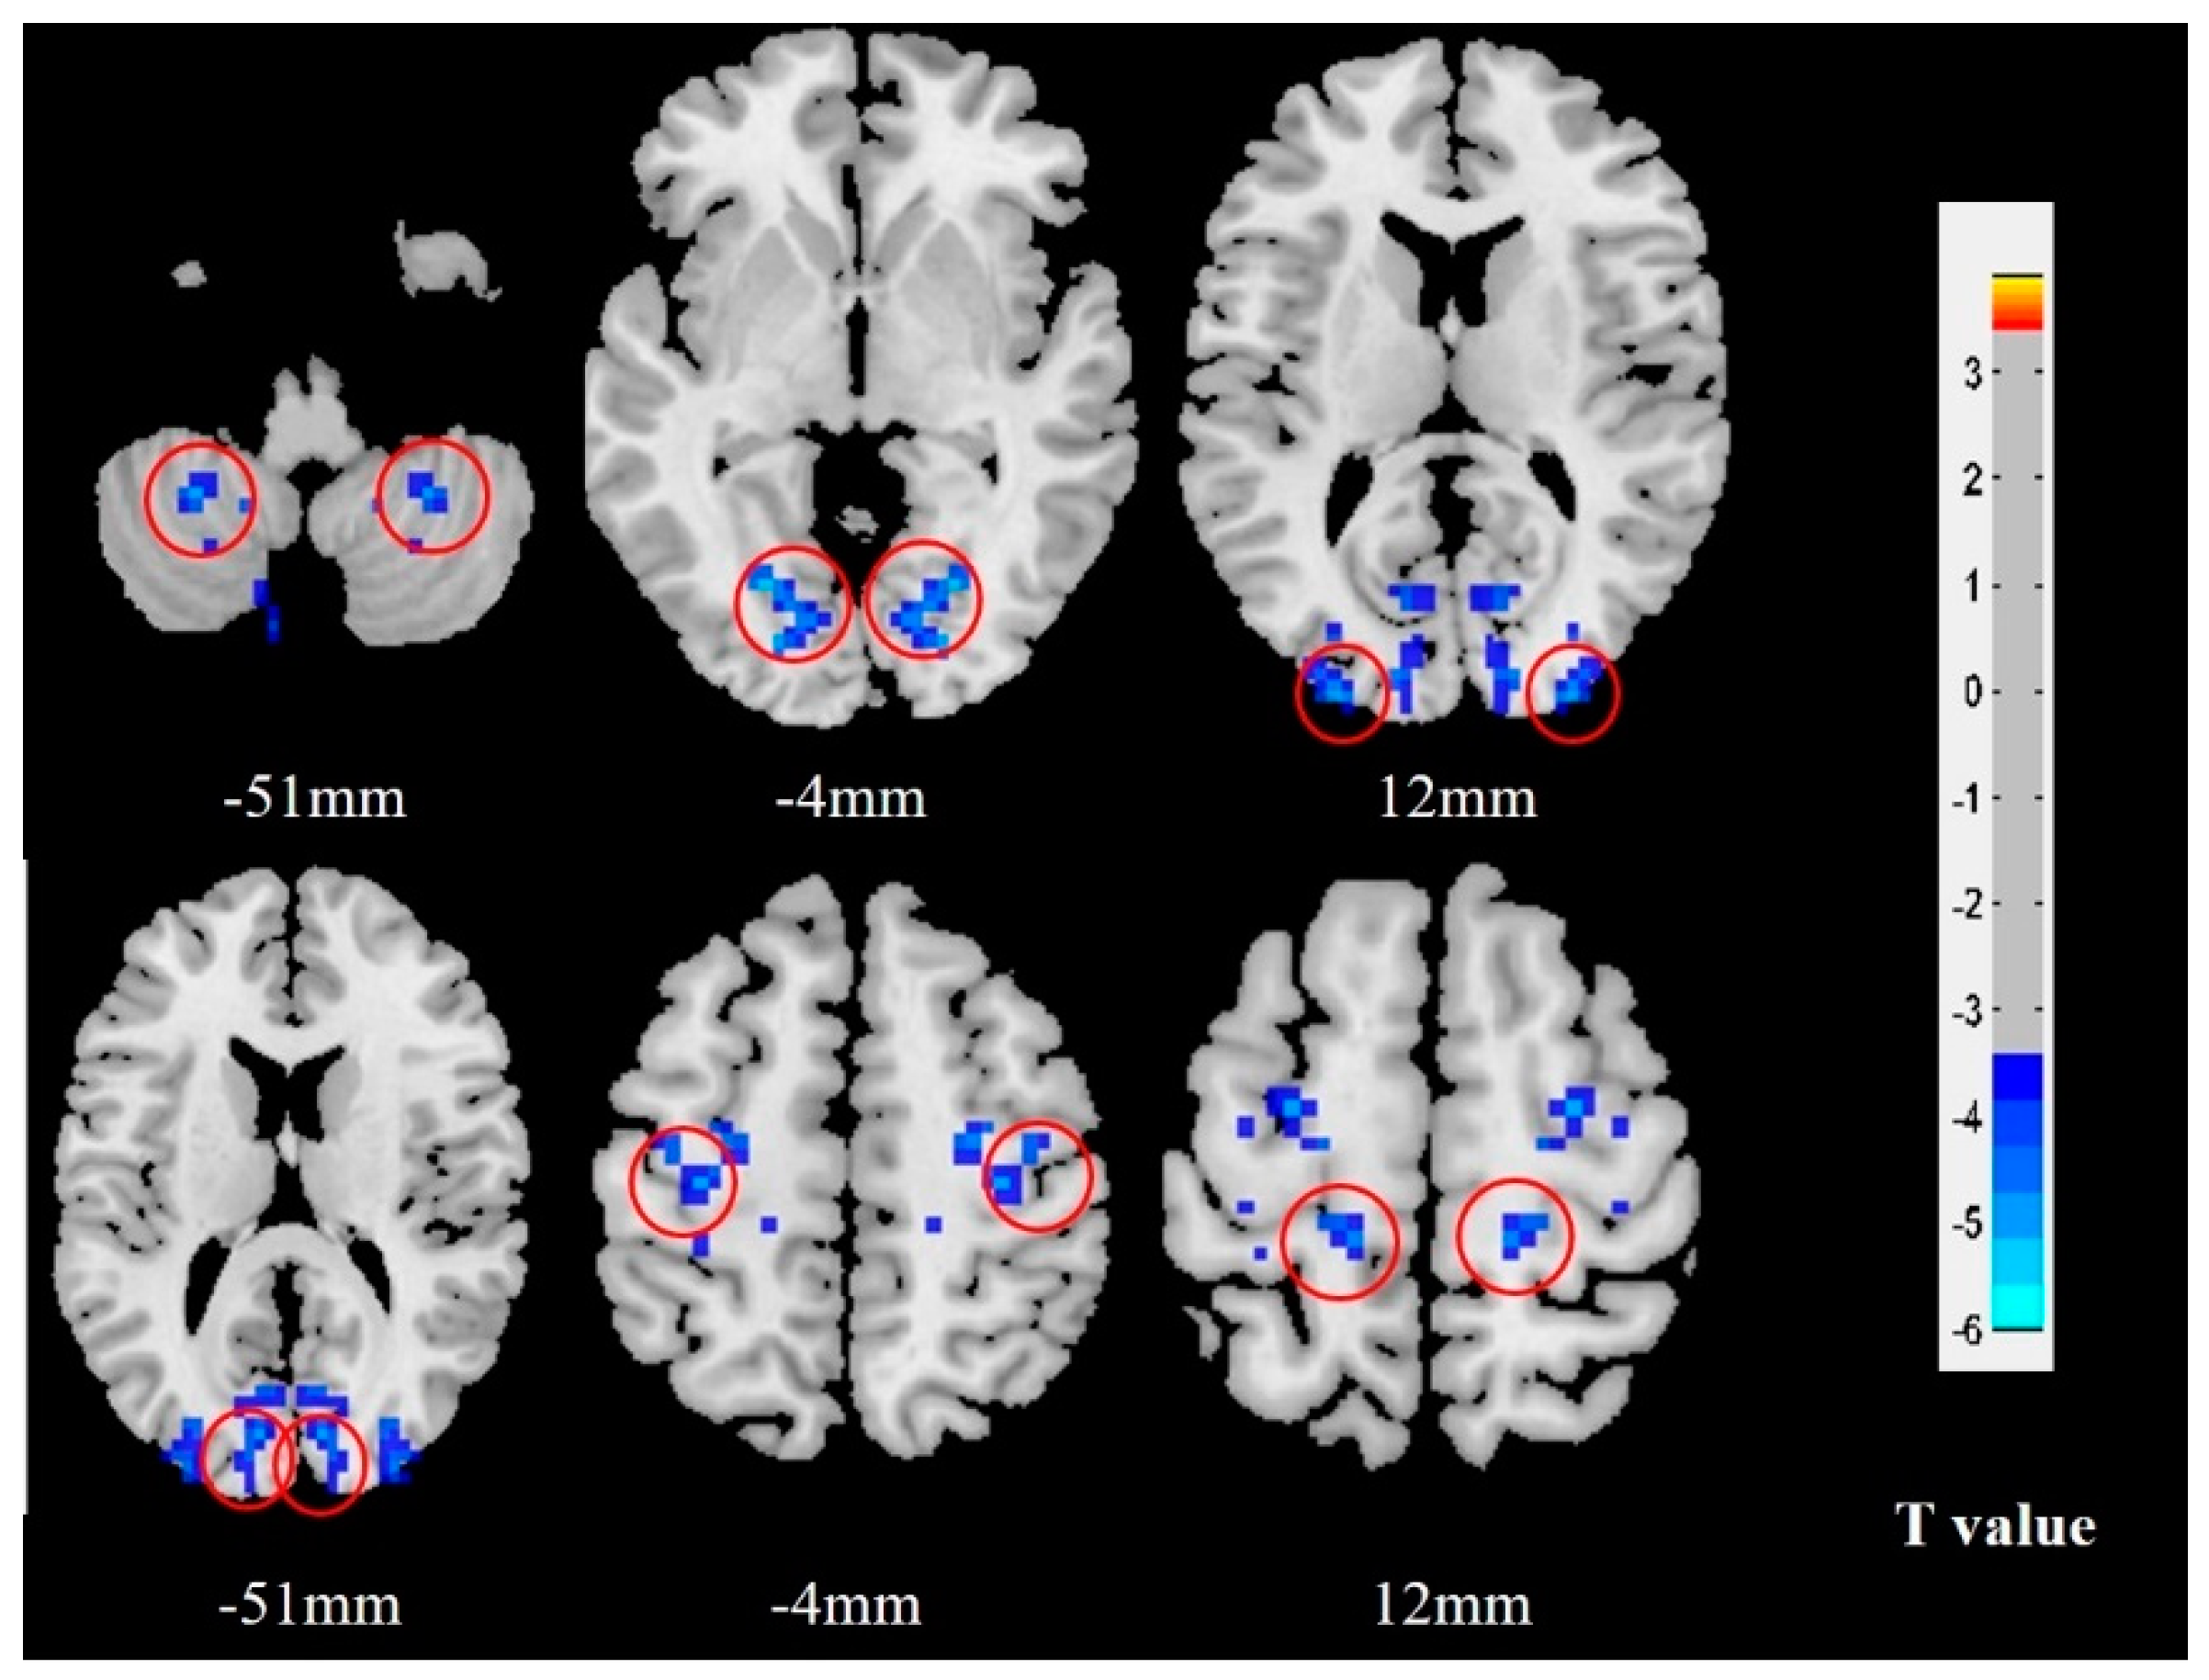

Compared with HCs, MwoA patients exhibited decreased VMHC in the bilateral cerebellum_8, lingual gyrus, middle occipital gyrus, cuneus, precentral gyrus and postcentral gyrus. There were no increases in VMHC in the brain regions of migraine patients with migraine compared with the HCs (Table 2 and Figure 2).

Figure 2.

VMHC results in female MwoA patients relative to HCs. Brain regions with notable alterations in VMHC are indicated with red circles. The blue color represents deactivation of neural activity. MwoA patients demonstrated significantly decreased VMHC in the bilateral cerebellum, lingual gyrus, middle occipital gyrus, cuneus, precentral gyrus and postcentral gyrus compared with HCs. Abbreviations: VMHC, voxel-mirrored homotopic connectivity; MwoA, migraine without aura; HCs, healthy controls.